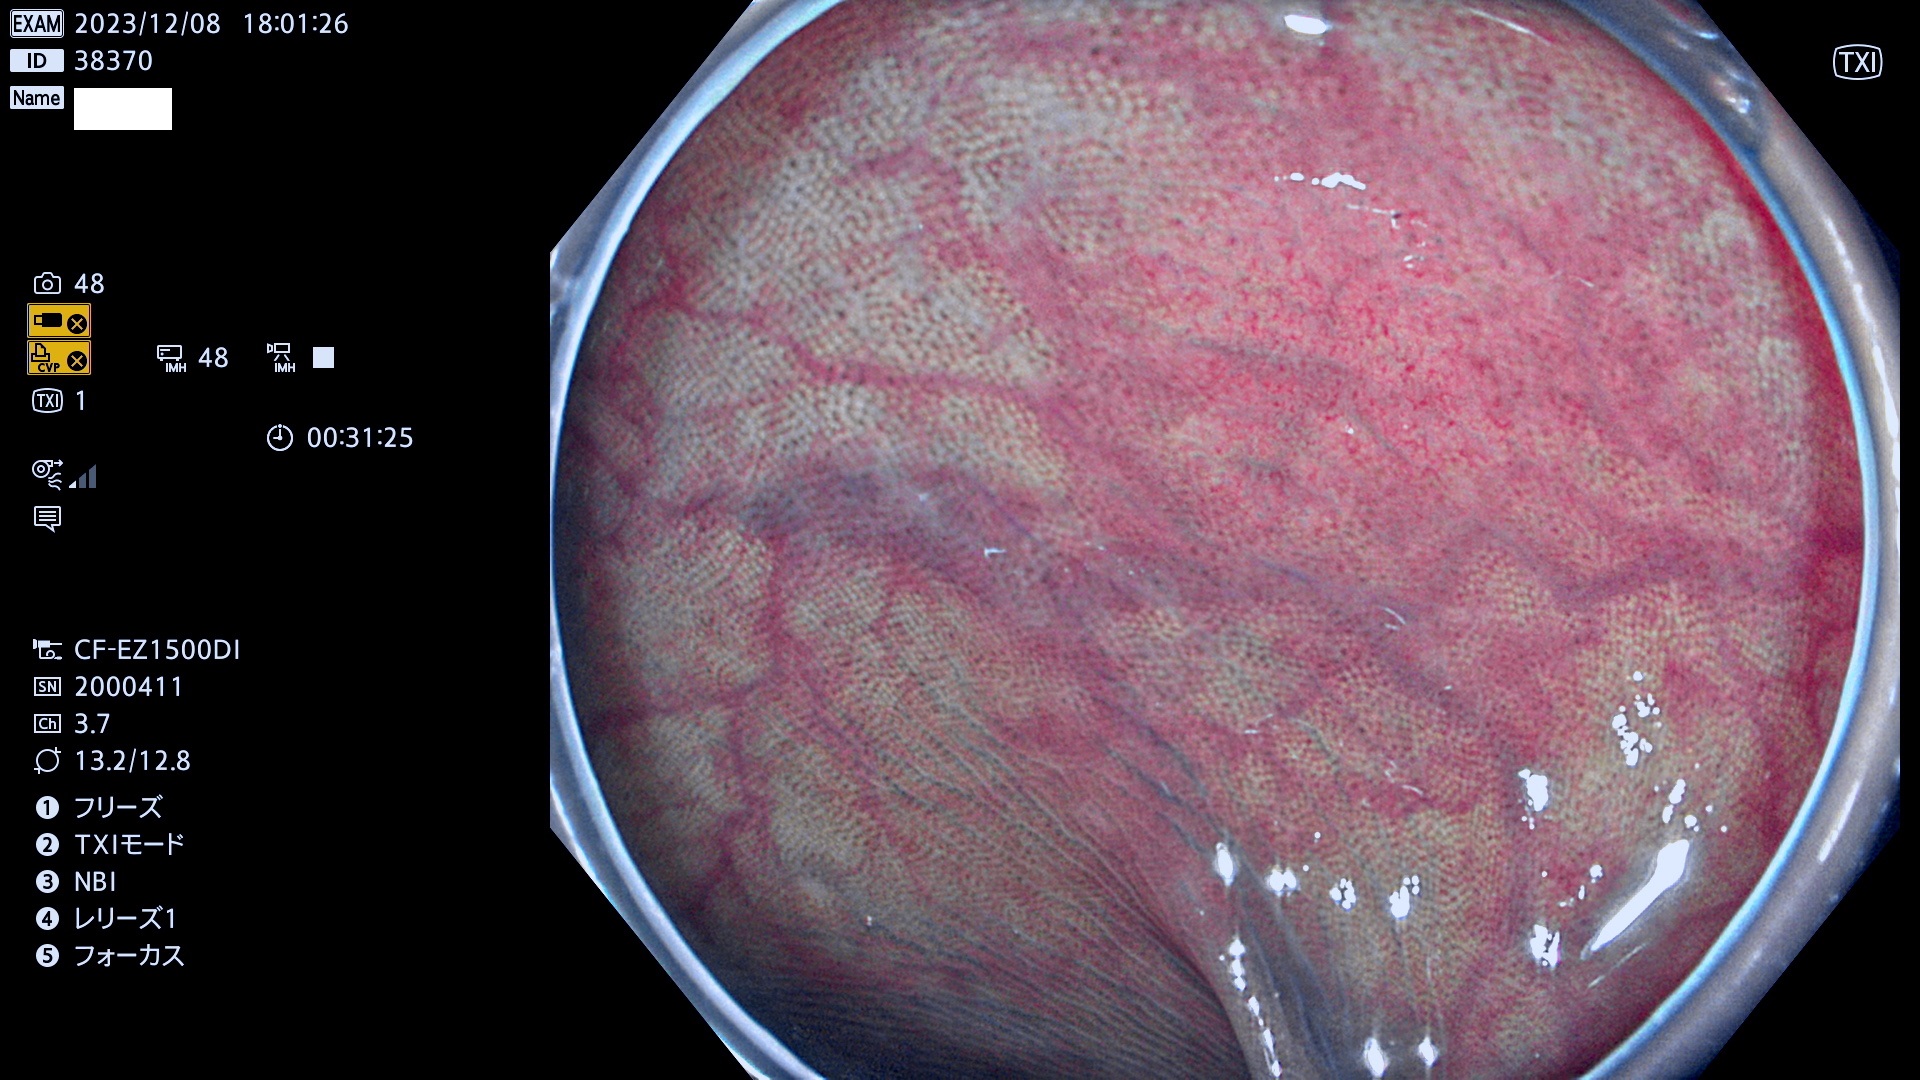

今週のUb、Uc型腺腫

表面型腺腫(Flat Adenoma)の中で、完全に平坦な物をUb、陥凹している物をUcと呼びます。平坦隆起型(Ua)よりも、発見が難しく危険な病変です。このタイプは「内視鏡後・大腸癌の重要犯人」であり、この発見率は「腺腫発見率」よりも、重要な意味があります。

毎週の検査(木・金・土・日)に発見されたUb、Uc型・腺腫を、その週の日曜の夜にUPし1週間、提示します。

抽出の対象期間 2023年12月7日(木)〜12月10(日)の4日間(48件の検査)12件

上記と同一病変